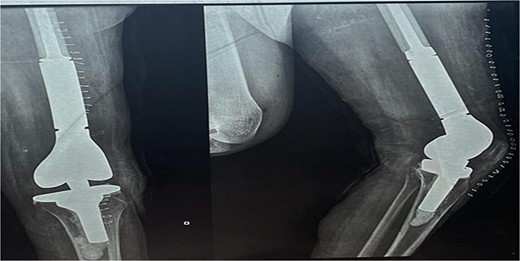

A 28-year-old female patient in her first trimester of pregnancy presented in our outpatient department with a complaint of persistent left knee pain for the past two years accompanied by a marked swelling around the left distal thigh region for the past 6 months. She had a previous X-ray that revealed an aggressive, Enneking stage III osteolytic lesion involving the medial femoral condyle, characterized by a shallow bubble appearance and a narrow zone of transition (Figs 1 and 2). A biopsy of the lesion was undertaken 6 months before the initial presentation and showed an aggressive GCT.

The X-ray shows a distal femur osteolytic lesion with a soap bubble appearance, a narrow zone of transition, a soft tissue component, and a sparing knee joint in the X-ray taken 6 months before pregnancy.

X-ray that was taken 4 months before presentation showing the tumor was very aggressive with a narrow zone of transition, and mass is progressively increased.

The X-ray after surgery showed a mega prosthesis with good implant alignment.